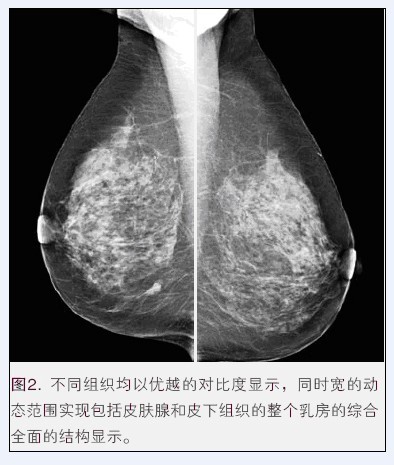

乳腺X射線機作為如今各大醫院及機構主要的放射科設備之一,為女性健康提供了先進的檢測平臺,是如今醫學領域檢測患者乳腺癌變等狀況的必備醫療器械。然而,隨著醫學事業的快速發展,醫療器械行業發生了翻天覆地的變化,生產乳腺X射線機的醫療器械公司也越來越多,那么到底乳腺X射線機哪個牌子好呢?

這就不得不提到國內具有較高知名度的普朗醫療。普朗BTX-9800系列乳腺機是如今女性乳腺癌早期診斷的金標準,不僅可以發現0.1毫米的鈣化點,還能夠有效提示癌前病變,是乳腺炎癥、乳腺增生、乳腺纖維瘤等疾病監測的必備設備。更多資料,請點擊產品圖下方的紅色產品名稱進入指定頁面: